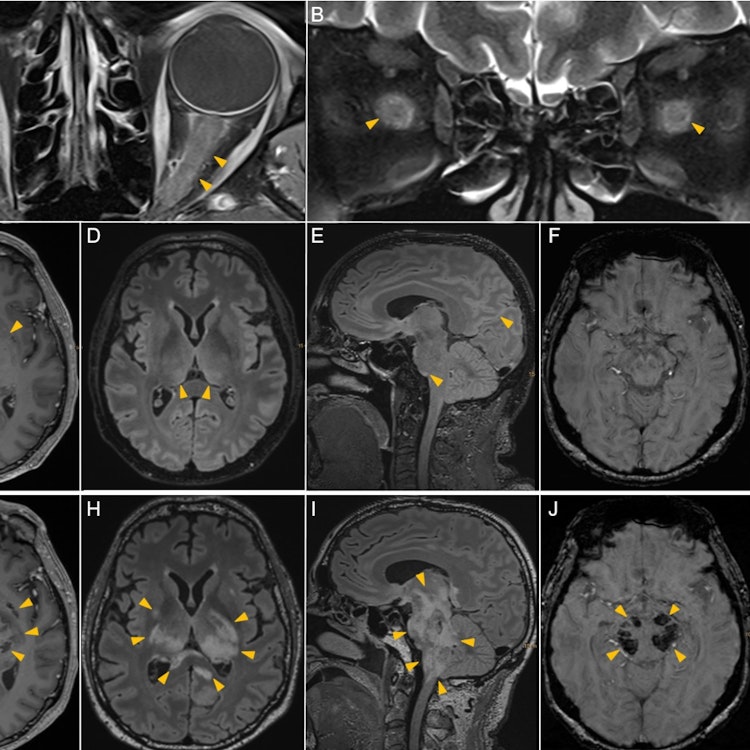

Dear Editor, We read with interest the recently published article ‘MOG antibody-associated encephalitis in adult: clinical phenotypes and outcomes’ by Lee et al.1 The authors illustrate three core disease phenotypes consisting of cortical encephalitis, limbic encephalitis and acute disseminated encephalomyelitis (ADEM), showing good response to immunosuppressive treatment and positive long-term outcomes. However, we would like to raise attention towards an emerging MOG antibody-associated clinical presentation characterised by a highly aggressive disease course with unfavourable prognosis suggestive for acute haemorrhagic leucoencephalitis (AHLE). MOG antibody-associated disease (MOGAD) is a recently described autoimmune disease of the central nervous system. Accumulating evidence suggests that MOGAD has a remarkably heterogeneous spectrum. Besides cases of cerebellitis and autoimmune encephalitis, also a syndrome of encephalitis with steroid-responsive seizures, so-called FLAMES (FLAIR-hyperintense lesions in anti-MOG-associated encephalitis with seizures), is now recognised to be a specific feature of MOGAD. Interestingly, MOGAD can present with a monophasic clinical course in 50% of cases, which sets it clearly apart from multiple sclerosis and neuromyelitis optica spectrum diseases (NMOSD).